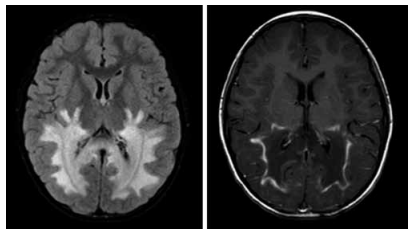

Menino de 6 anos de idade apresenta quadro progressivo de comprometimento cognitivo e espasticidade. As imagens por ressonância magnética do crânio FLAIR e T1 com contraste, respectivamente, demonstram as alterações a seguir.

O diagnóstico mais provável é: